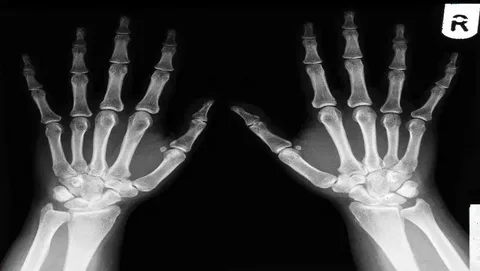

El bileği kırıkları, hem günlük yaşamda hem de spor aktiviteleri sırasında sık karşılaşılan ortopedik yaralanmalar arasında yer alır. Özellikle düşmeler sonucu el üzerine yük binmesi, el bileği kemiklerinde kırıklara yol açabilir. Bu tür kırıklar genellikle alçı, atel veya cerrahi yöntemlerle tedavi edilir. Ancak tedavi sürecinin önemli bir parçası da rehabilitasyon sürecidir.

El bileği kırığı sonrası hareket kısıtlılığı, kas güçsüzlüğü ve fonksiyon kaybı görülebilir. Bu nedenle fizik tedavi uygulamaları, el ve bilek fonksiyonlarının yeniden kazanılmasında kritik bir rol oynar. Günümüzde gelişen teknoloji ile birlikte robotik rehabilitasyon, el ve üst ekstremite rehabilitasyonunda destekleyici bir yöntem olarak kullanılmaktadır.

El bileği, radius ve ulna kemiklerinin distal uçları ile el kemiklerinin birleştiği kompleks bir eklemdir. Bu bölge günlük yaşamda sık kullanılan ve hareket kabiliyeti yüksek bir yapıdır.

Evet, el bileği kırıkları sonrasında uygun hastalarda robotik rehabilitasyon uygulanabilir. Özellikle üst ekstremite rehabilitasyonu için geliştirilen robotik sistemler, el ve bilek hareketlerinin yeniden kazanılmasına yardımcı olabilir.